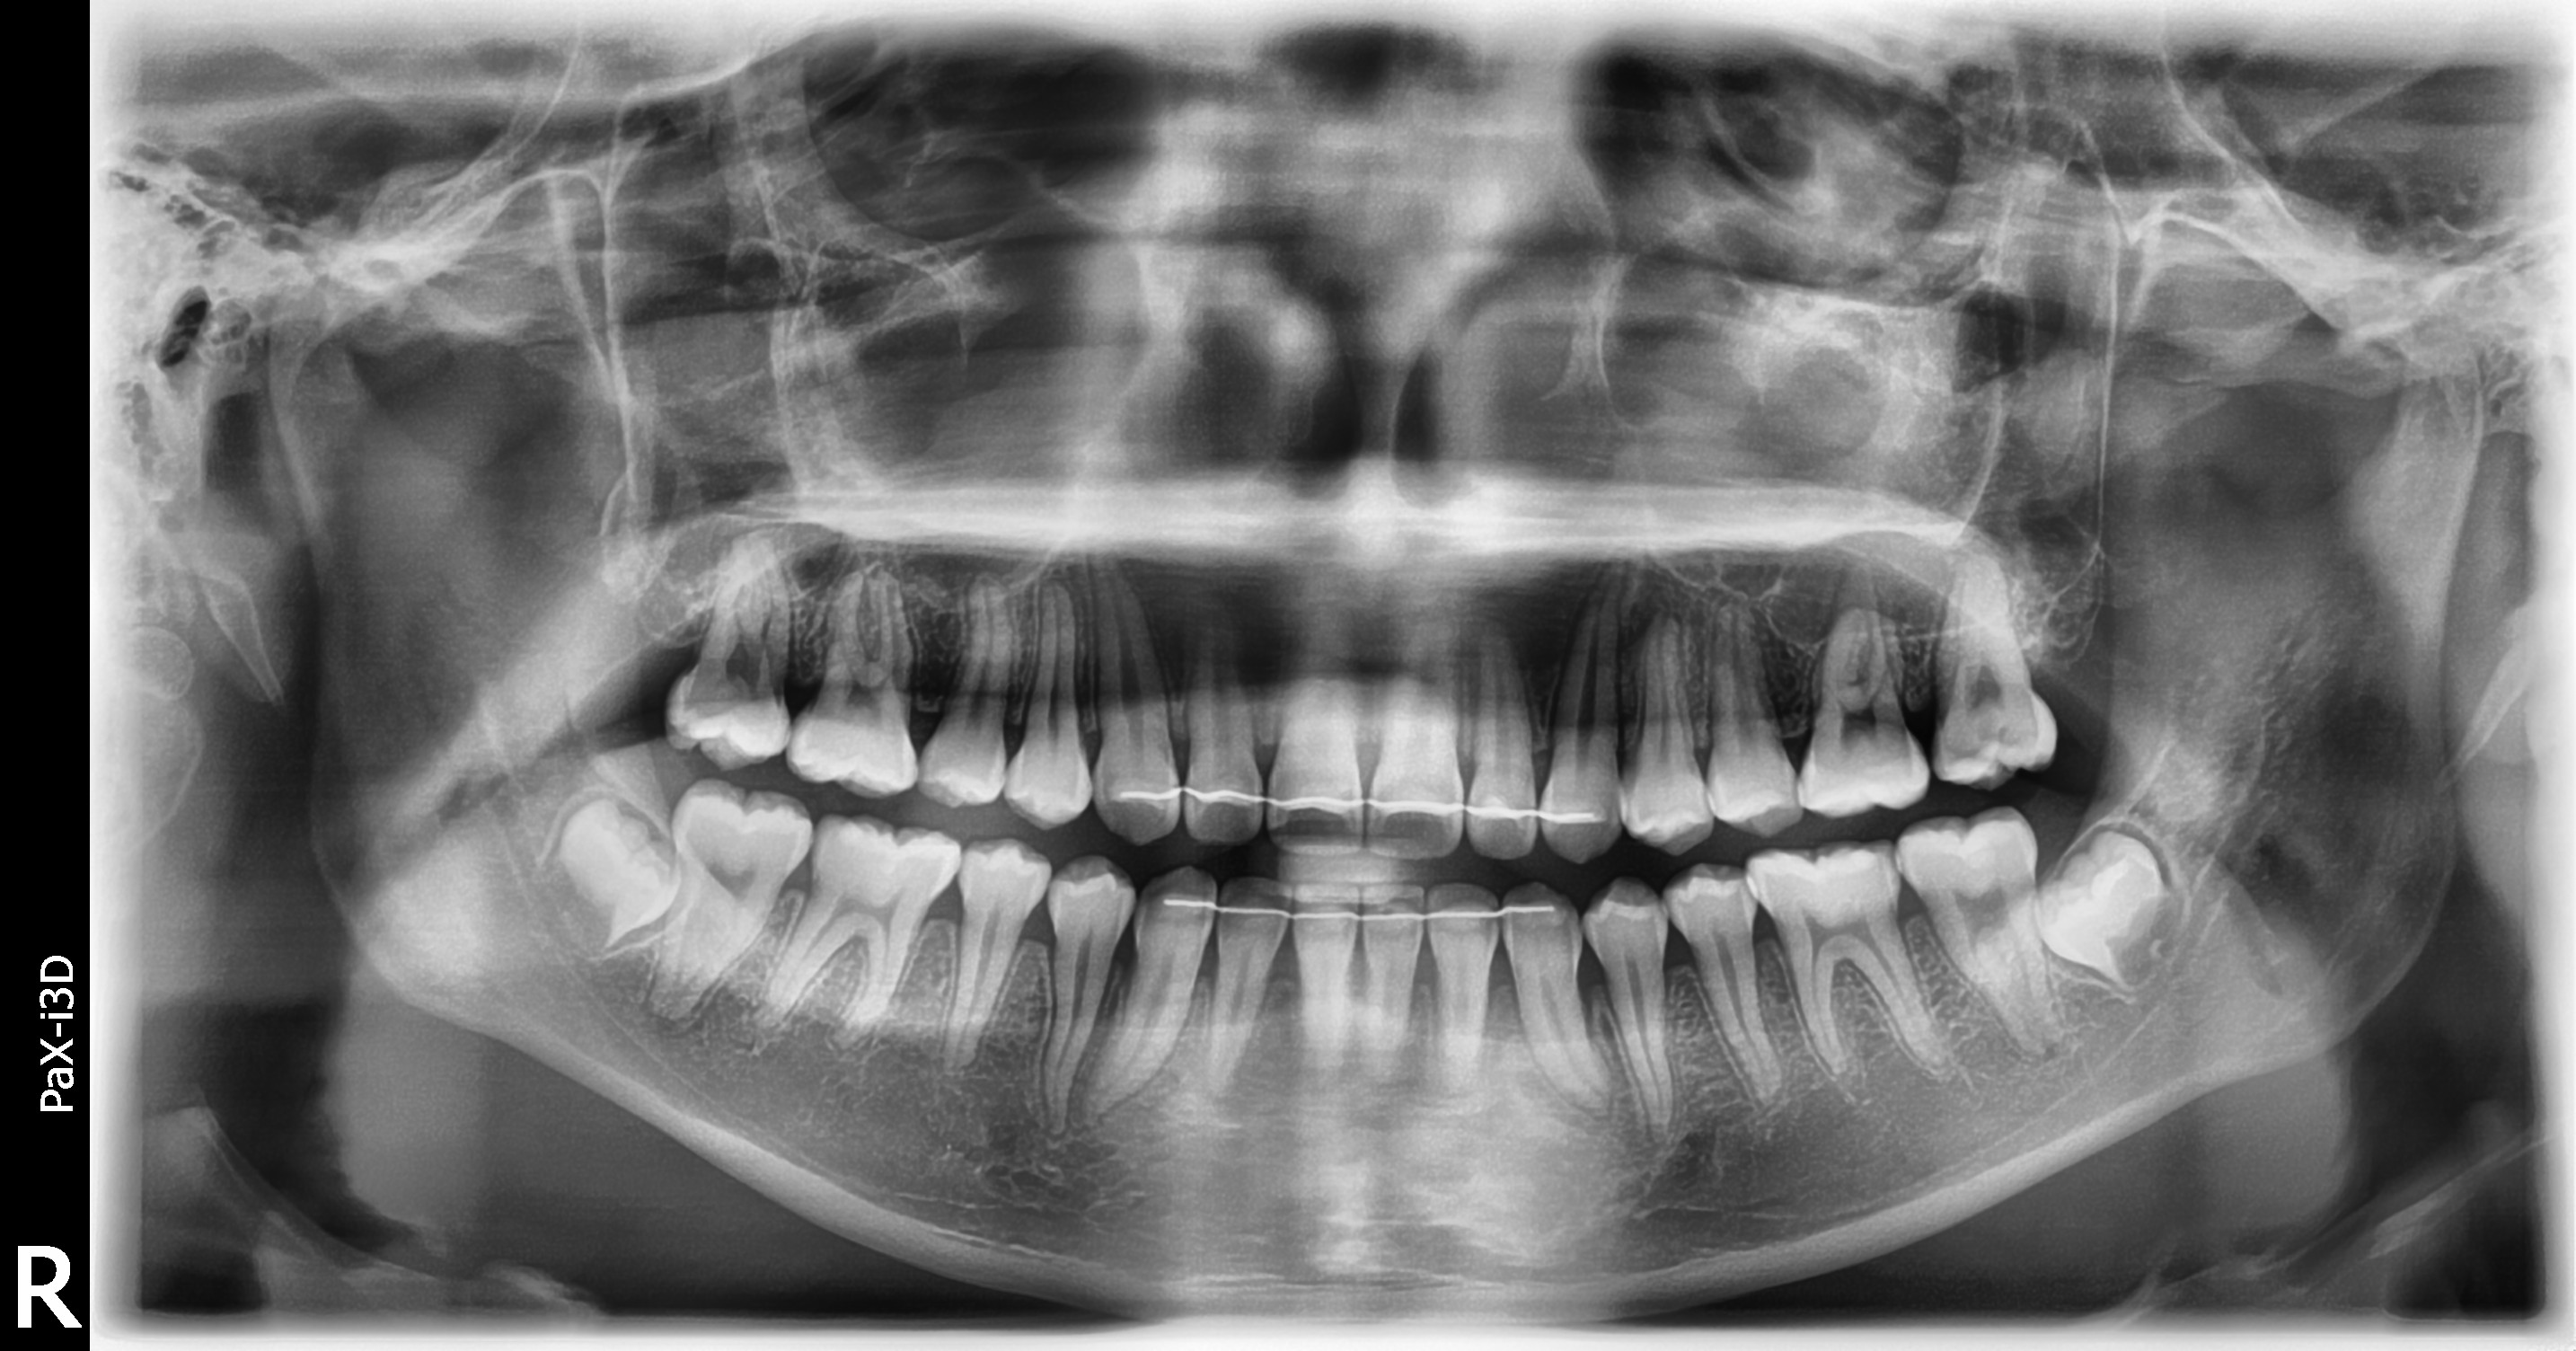

맹출유도교정

보철교정